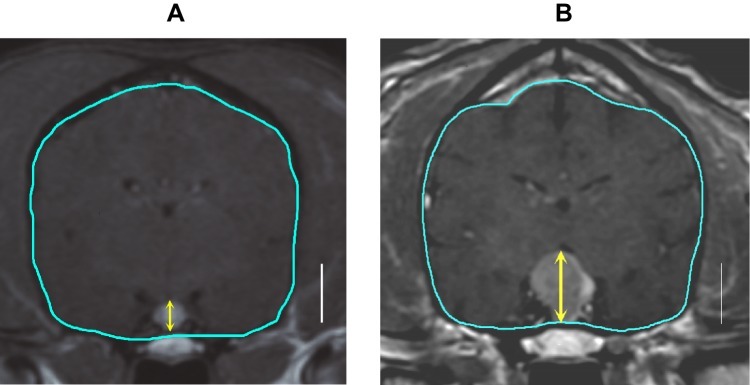

Measurements of pituitary brain ratio (PBR).

PBR can be calculated by both CT and MRI.

Image that contained the largest cross section of the pituitary

A

• the edge of the brain (shown in blue line)= AREA

• height of the pituitary gland was measured (shown in yellow arrow).

PBR = (height of the pituitary gland)/(cross sectional area of the brain) x 102. (Dr. Kooistra HS in1997)